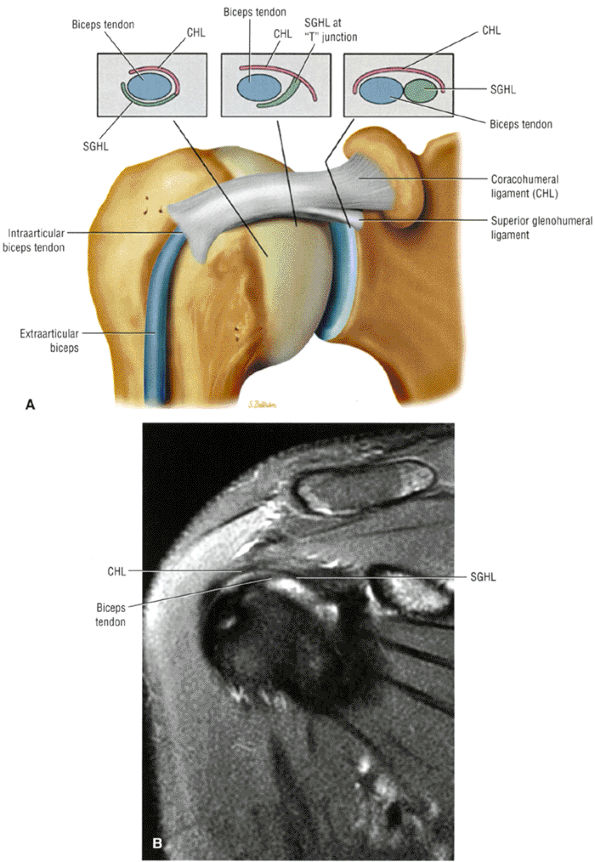

FIGURE 8.94 ● (A) The biceps pulley complex is sectioned in the sagittal plane at the level of the proximal, middle, and distal rotator cuff interval. The confluence of the CHL and SGHL occurs at the middle and distal aspects of the rotator interval. A T-shaped junction is formed between the SGHL and CHL at the mid-interval, superior to the humeral head. An anterior U-shaped sling is shown at the distal interval at the entrance to the bicipital groove. (B) An anterior coronal FS PD FSE image demonstrates the biceps tendon contained between the CHL and SGHL components of the biceps pulley.

FIGURE 8.95 ● Sagittal MR arthrograms. (A) The anterior biceps sling is formed by the confluence of the CHL and SGHL anterior to the LHBT. (B, C) The T-shaped junction of the SGHL and CHL at the midportion of the rotator cuff interval.